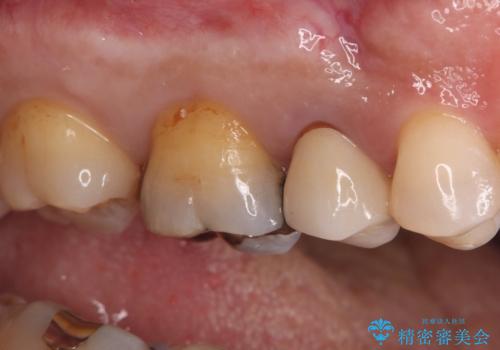

- 長年使用してきた奥歯の古い銀歯のやりかえを主訴にご来院されました。診査の結果、銀歯の下の歯質が薄くなっている部分があり、今後強い力が加わると歯が割れてしまう(破折)リスクが高いと判明しました。このリスクを回避し、歯を長期的に守るため、歯全体をしっかり覆う**セラミッククラウン(被せ物)**による修復を提案。機能的な強度と自然な見た目の両立を目指しました。

治療では、まず古い銀歯を慎重に取り外し、内部の虫歯の有無を確認しました。その後、残っている歯質を保護し、強度を高めるために、適合性に優れたオールセラミッククラウンを作製・装着しました。

強度: 歯全体を覆うため、咬合力による歯への負担を分散させ、破折リスクを大幅に軽減します。

審美性: 天然歯に近い透明感と色調を持つため、銀歯の時と比べて格段に自然で美しい見た目になります。